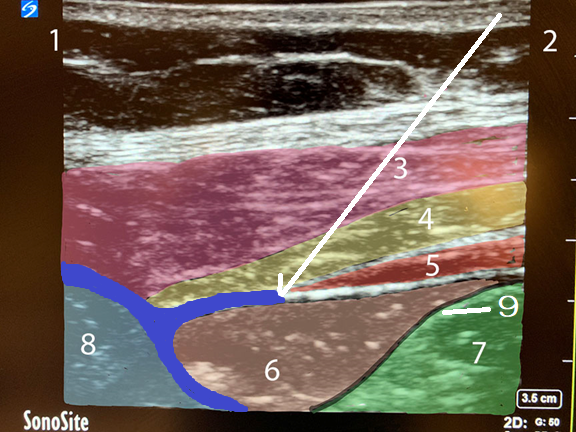

QL Block Lateral Approach Needle Path Image

White Arrow: Needle Path

Blue Area: Local Anesthetic

1. Posterior

2. Anterior

3. External Oblique Muscle

4. Internal Oblique Muscle

5. Transverse Abdominis Muscle

6. Pararenal Fat

7. Peritoneum

8. Quadratus Lumborum Muscle

9. Transversalis Fascia